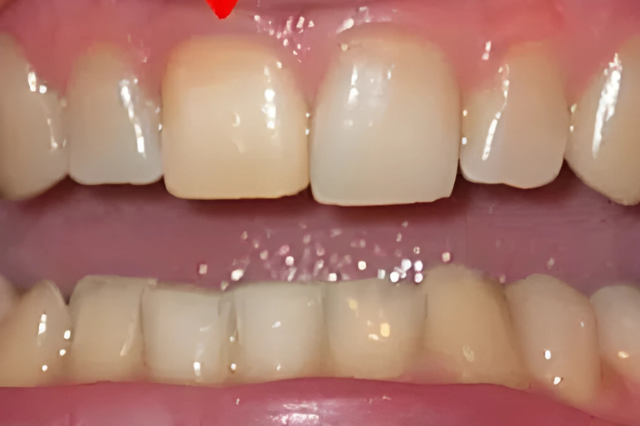

Felső fogsor szabályozás

A páciens felső metszőfogai erősen torlódtak, ami esztétikai és funkcionális problémát okozott. A kezelés után harmonikus, szabályos fogív alakult ki.